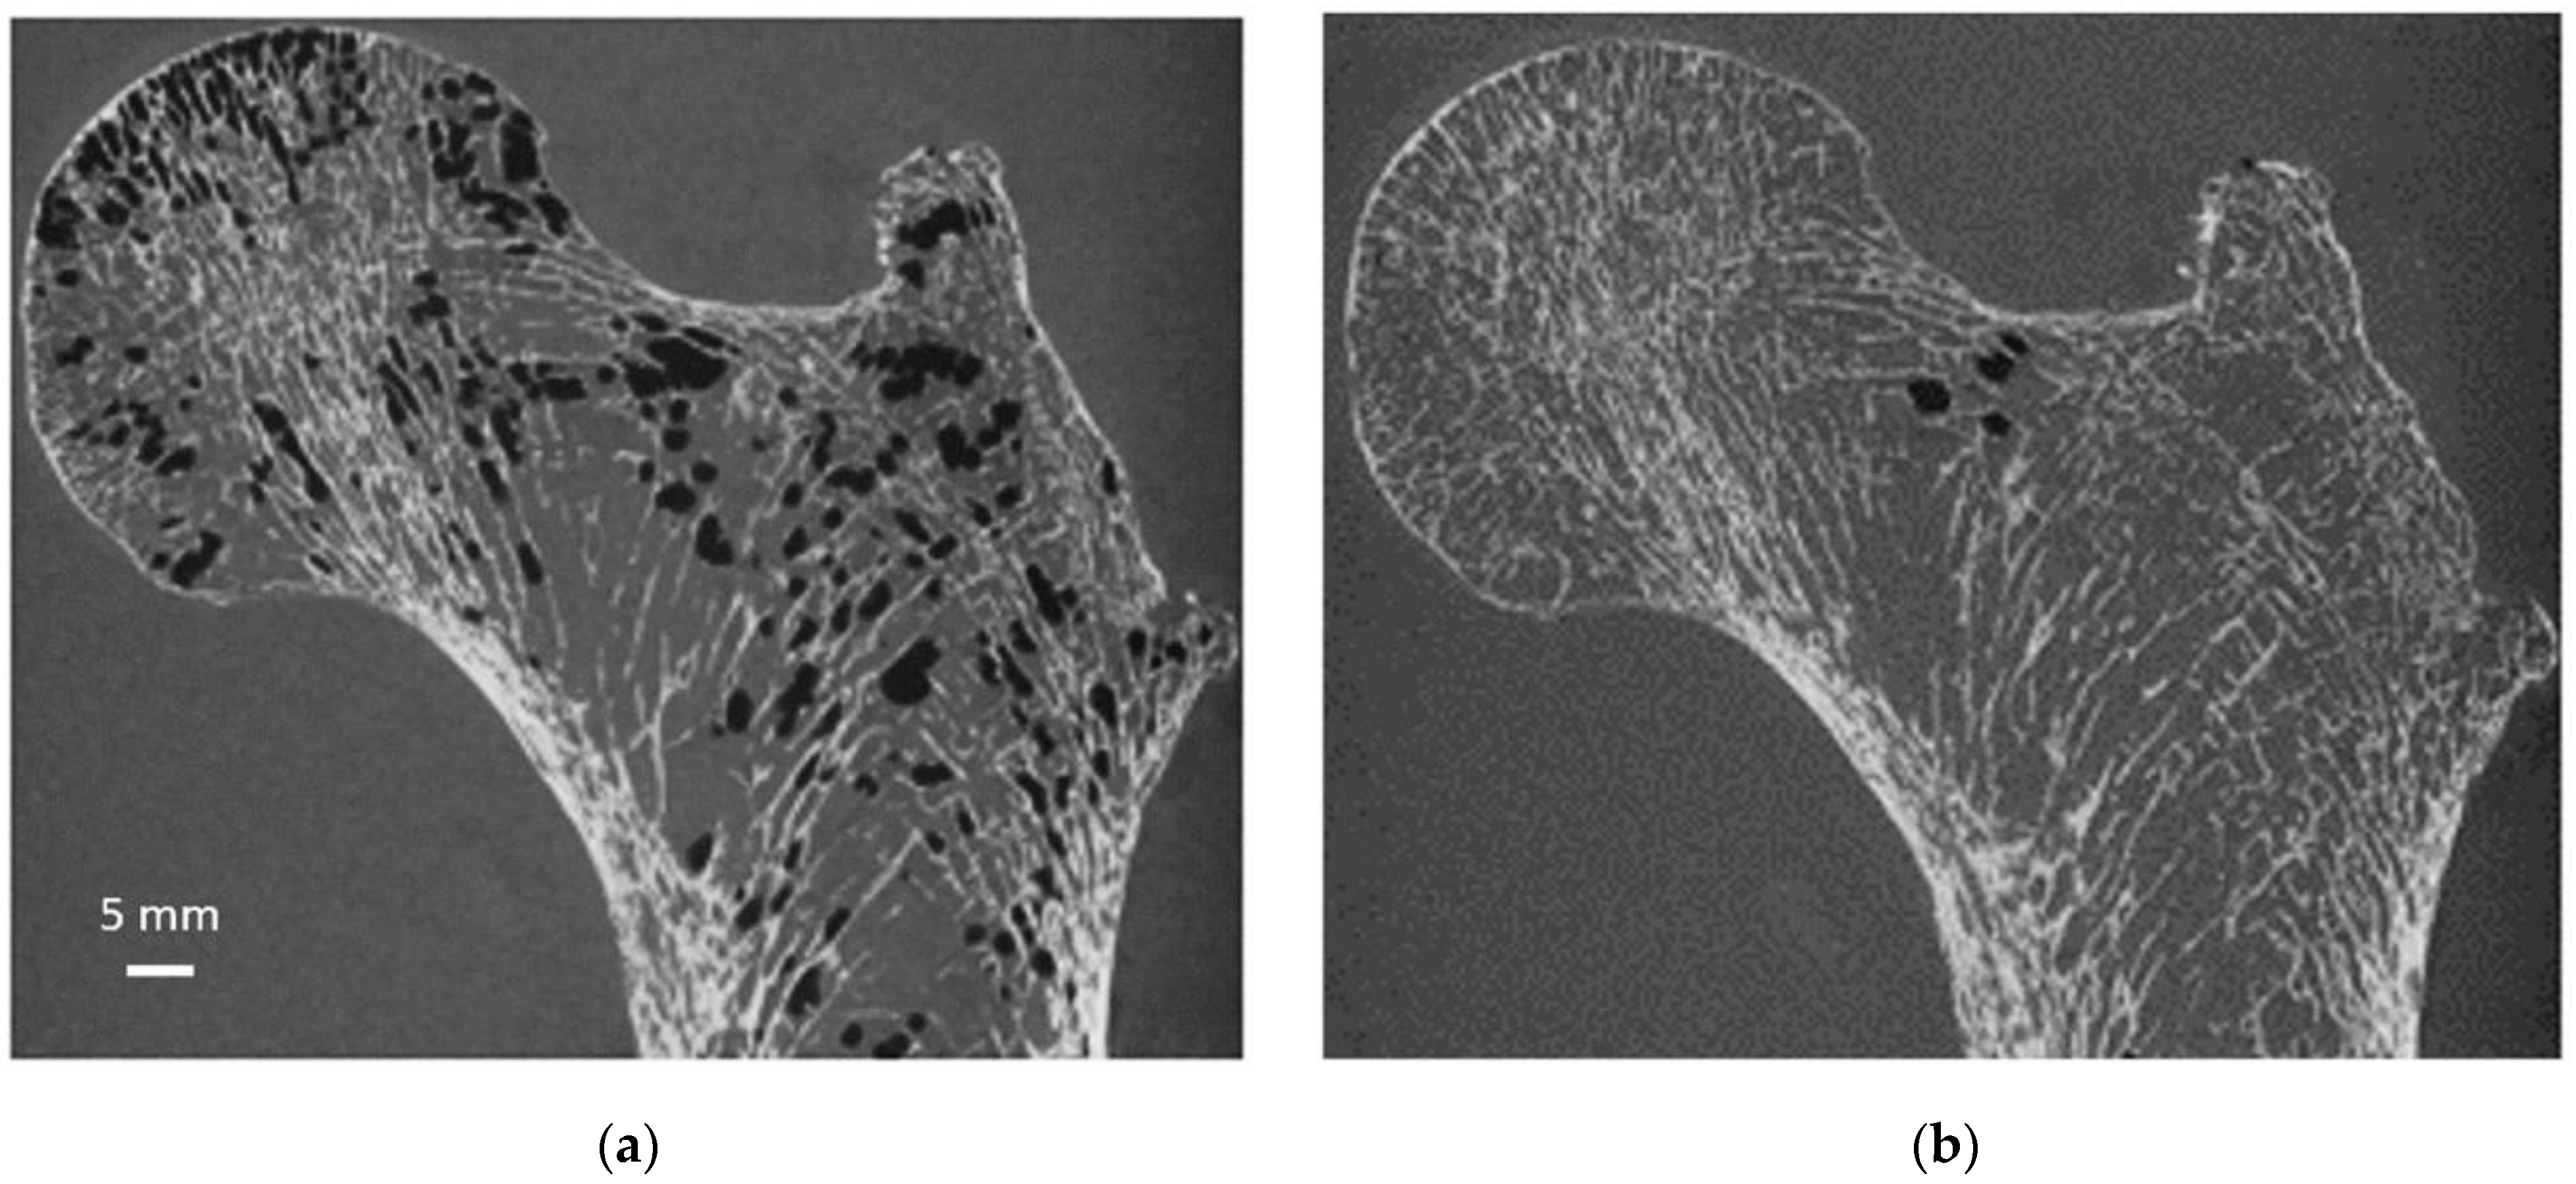

Figure 6. Same coronal µCT plane before and after sample preparation. Same S1 µCT coronal plane before (a) and after (b) the application of our sample preparation technique and acquired at 0.051 mm isovolumetric resolution.

As illustrated in Figure 6, air bubbles were clearly visible as darker pixels in the μCT images. The corresponding air volume present inside S1 was 12.4 cm3 (Table 1). During the vacuum procedure, the movement of air bubbles from the bottom cross-section was clearly visible. Three vacuum cycles were applied, and the total amount of air bubbles still present in the bone microstructure was greatly reduced (<0.5%) of the total bone marrow volume (Table 1). Moreover, the residual amount of air bubbles after each vacuum cycle was evaluated in the case of S1. The results showed that the first vacuum cycle led to a significantly large reduction (98.8%) in air volume, while the remaining air volume was completely removed after two additional cycles (Figure 6 and Table 1).

To quantify the effect of the successive pumping cycles, 3D μCT acquisition was performed before and after each cycle, reporting the total volume of bubbles still present inside the bone microarchitecture. The segmentation of air bubbles was straightforward because bone, bone marrow and air have very different X-ray absorption properties. Air bubble volume (Ab.V in μm3 and in %) was computed within the complete 3D bone volume. This special preparation protocol is specifically dedicated to the assessment of cadaveric femurs since no air bubble inclusion is present in vivo. However, the MRI protocol was designed to be applicable for in vivo acquisition. Therefore, clinical application and analysis of in vivo bone microarchitecture could be performed.